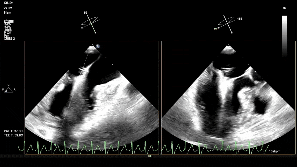

随后将可操控导引导管(SGC)及二尖瓣夹输送系统(CDS)送入左心房。仔细调整XTW二尖瓣夹的轨迹和方向后,进行首次夹合,超声提示仍存在少量二尖瓣反流,考虑为后侧瓣叶捕获不足所致,且侧边瓣叶仍存在明显脱垂。遂打开夹臂,在左心房内调整夹子位置,向后侧、外侧移动,以捕获更多后侧瓣叶,再次夹合,成功解决反流与脱垂问题,测得术后平均压差为4mmHg,手术圆满成功。

术中影像

第一次夹合后3D

第一次夹合后3D彩

调整瓣膜夹位置

再次捕获瓣叶

第二次关闭瓣膜夹

测量前后瓣距离

释放夹子

夹子释放后反流降至轻度

3D下组织桥稳定

3D下上彩

术后平均压差为4mmHg